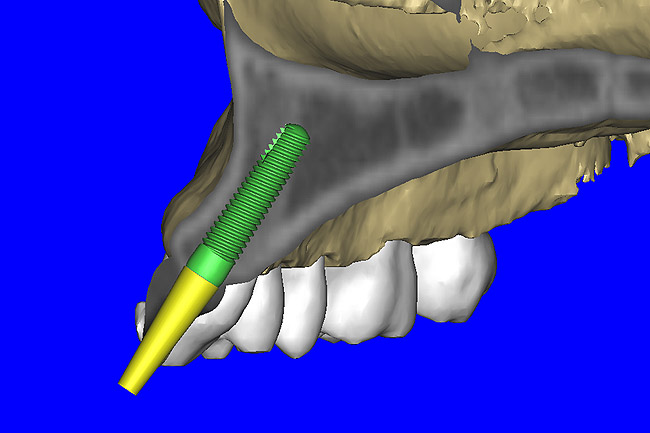

After the basic plan had been established, it was re-evaluated using interactive 3D images. The reconstructed 3D view of the maxilla clearly illustrated the extent of the bilateral facial concavities, and the root eminences of the adjacent and posterior teeth (Figure 7A). The placement of the virtual implants then was evaluated to ensure that the facial cortical plate was not perforated (Figure 7B). The implants were labeled individually as “7” and “10,” with the simulated yellow abutment projection indicating the facial-lingual inclination through the bone to the level above the incisal edge of adjacent teeth. The ability to gain a better understanding of these individual root forms can not be underestimated. The dental literature has suggested certain parameters for placing implants near teeth and implants next to other implants. However, there is little scientific 3D documentation to support these suggested rules.5-10 The use of an interactive treatment-planning software application permits closer scrutiny of previously difficult-to-visualize areas, and can now be used to redefine perceptions of spatial positioning of implants, especially when in close proximity to natural tooth roots, vital anatomy, and adjacent implants.27-29

Figure 7a  The 3D reconstruction showed (A) the facial concavities and root eminences, and allowed (B) for evaluation of virtual implant placement to ensure the facial cortical plate was not perforated.

Figure 7a

Figure 7b  The 3D reconstruction showed (A) the facial concavities and root eminences, and allowed (B) for evaluation of virtual implant placement to ensure the facial cortical plate was not perforated.

Figure 7b